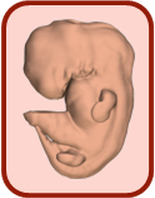

Нидерландские ученые создали трехмерный атлас пренатального развития человека в первые два месяца после зачатия. Об этом сообщает 3D Embryology.

Ученые Академического медицинского центра в Амстердаме идентифицировали и промаркировала 150 структур и органов тела эмбрионов, после чего реконструировали их трехмерные компьютерные модели.

Результаты исследований сгруппировали в единый атлас развития эмбриона в период от 15-17 до 56-60 дня после зачатия.

Все модели были классифицированы по стадиям развития и превращены в интерактивный формат 3D-PDF, который находится в свободном доступе.

Скачать модели можно с сайта проекта. Уровне развития эмбриона распределены по стадиям, перейдя на которые можно увидеть модель и отдельные ее части.

Атлас позволяет рассмотреть как эмбрион в целом, так и его отдельные структуры, органы и системы.

Для более полного понимания ученые указали размеры эмбриона в миллиметрах и по сравнению с ладонью взрослого человека.

Как отмечается, работа над созданием атласа велась с 2009 года. Участие в ней приняла группа эмбриологов при содействии 75 студентов.